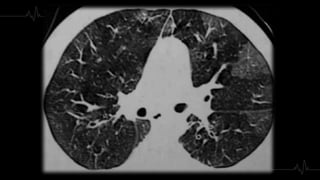

3. Extensión

4. AFECTACIÓN

PARENQUIMATOS

A● Inicialmente: Opacidad en vidrio

deslustrado, segmentaria, de morfología

triangular y base pleural.

● Con el paso del tiempo: Consolidación.

● Se puede identificar una atelectasia del

área afecta, la isquemia pulmonar provoca

una alteración del surfactante con colapso

secundario.

4. AFECTACIÓN PARENQUIMATOS A● Inicialmente:Opacidad en vidrio deslustrado, segmentaria, de morfología triangular y base pleural. ● Con el paso del tiempo: Consolidación. ● Se puede identificar una atelectasia del área afecta, la isquemia pulmonar provoca una alteración del surfactante con colapso secundario.